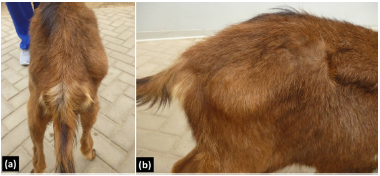

Findings of the clinical examination. In the clinical examination, the patient was evaluated at station, while walking and at a jog. The patient had a grade 2 claudication of the right hind limb (on a scale of 0 to 5: moderate lameness and clearly visible at the trot). A muscle hypotrophy of the hip and the right hind limb, as well as a notorious prominence of the lateral region on the greater trochanter of the femur were observed at the inspection of the pelvis (Figure 1).

Figure 1 Inspection in posterior (a) and right lateral (b) in a male alpine goat of 7 months of age with claudication of the right hind limb: A prominence is identified in the lateral region on the greater trochanter of the femur